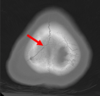

What imaging is used in this picture? [1]

A

dopamine transporter (DaT) - DaT scan